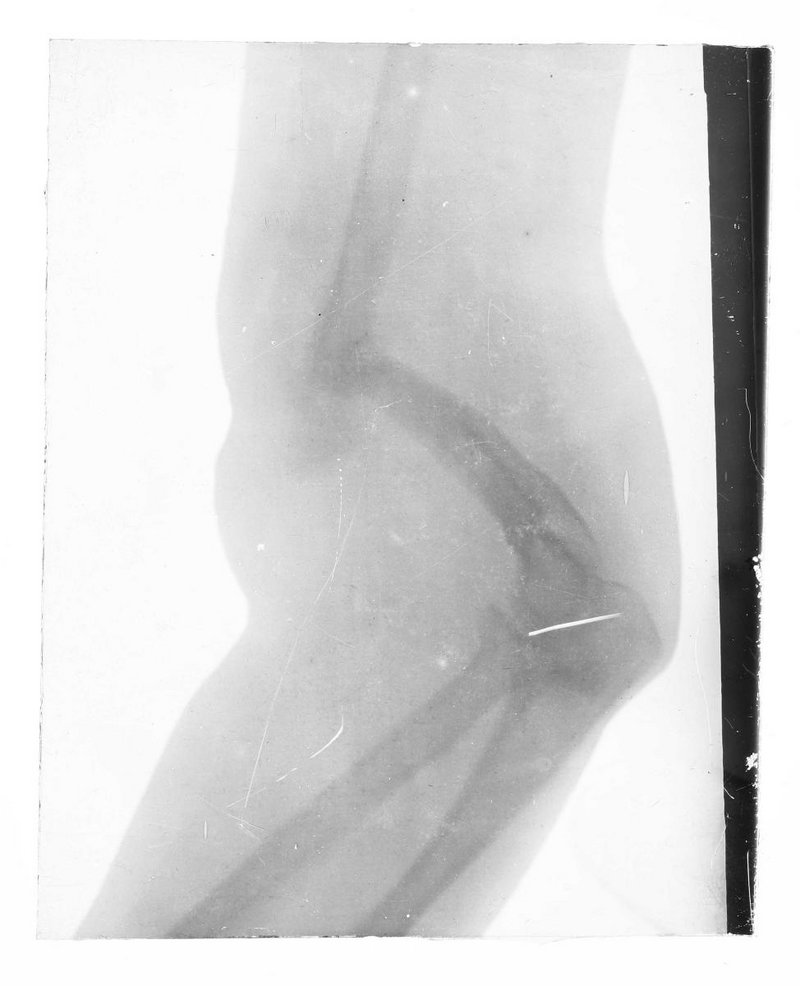

AT-MUW-FO-000101-0034

Medizinisches Fachgebiet

Radiologie

Objektart

Fotografie (FO)

Gegenstand

S/W, Glasdiapositiv

um 1896

Wien

Maße

Bildmaß 7,9 x 10 cm